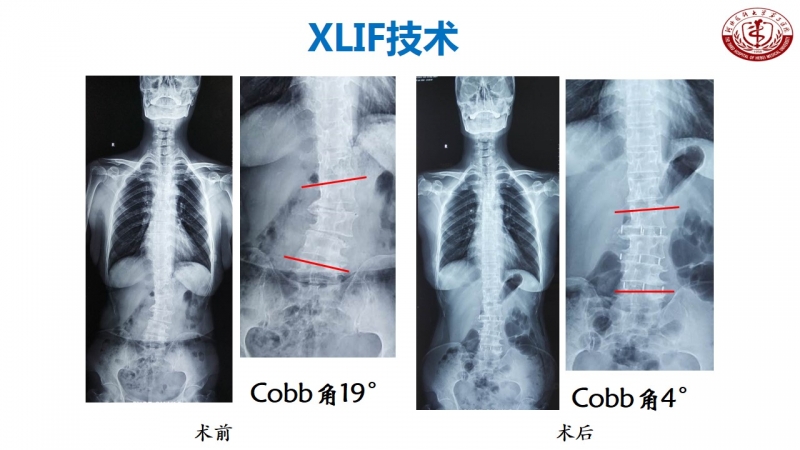

其实,在河北医科大学第三医院脊柱外科不乏这样的新技术创新。丁文元教授从医33年来,在脊柱疾病相关基础临床研究和治疗中做了大量的工作。

科室发展,未来可期

脊柱外科目前所开展的诊疗技术(滑动查看)

相信河北医科大学第三医院脊柱外科在新的学科带头人的领导下,不忘初心,砥砺前行,做好脊柱基础及临床研究,逐步提高学术影响力,攻克临床上各个难关,提升临床诊疗水平,使脊柱外科朝着精准化、微创化、显微化、智能化发展,造福更多患者。